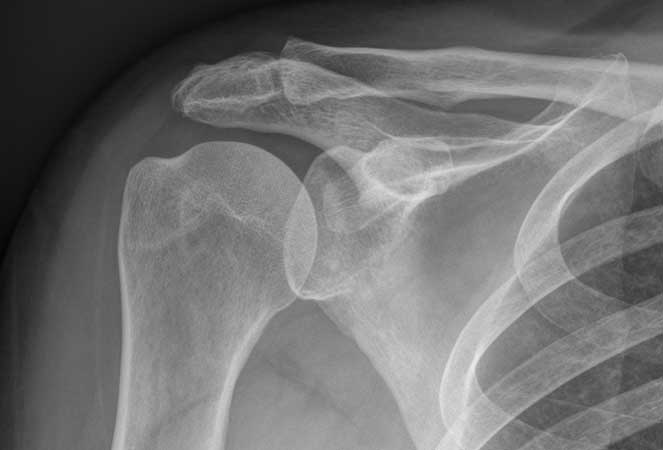

Uma radiografia do ombro, usualmente designada como raio-X (RX) do ombro é um exame de diagnóstico por imagem que usa radiação X, permitindo avaliar esta estrutura anatómica, principalmente em contextos de dor, traumas, luxações, etc..

O RX é um exame de diagnóstico que serve para auxiliar o médico no diagnóstico de diversas patologias (doenças), sendo frequentemente usado na presença de dor do ombro, em contextos de traumas, suspeitas de fraturas (ossos partidos), calcificações, luxações do ombro, artrose do ombro, etc..

Em termos de estruturas anatómicas, podem ser avaliadas a região proximal do úmero, a clavícula e a omoplata.